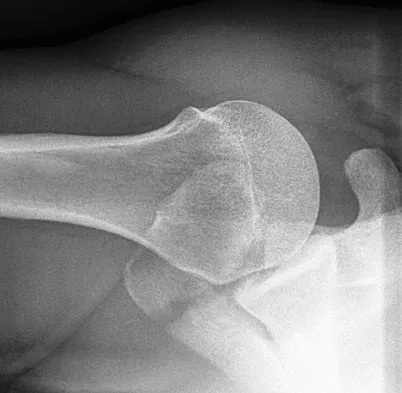

Figures 22a and 22b show the radiographs of a patient who reports stiffness of the hip and associated pain. Management should consist of

The patient has grade IV heterotopic ossification with the limb in an abnormal nonfunctional position. Treatment should consist of excision of the bone to restore hip motion and prophylaxis to prevent recurrent formation. The best time to excise the bone is controversial, with no conclusive evidence supporting early or late excision. Pellegrini VD Jr, Koniski AA, Gastel JA, Rubin P, Evarts CM: Prevention of heterotopic ossification with irradiation after total hip arthroplasty: Radiation therapy with a single dose of eight hundred centigray administered to a limited field. J Bone Joint Surg Am 1992;74:186-200.

- Warren SB, Brooker AF Jr: Excision of heterotopic bone followed by irradiation after total hip arthroplasty. J Bone Joint Surg Am 1992;74:201-210.